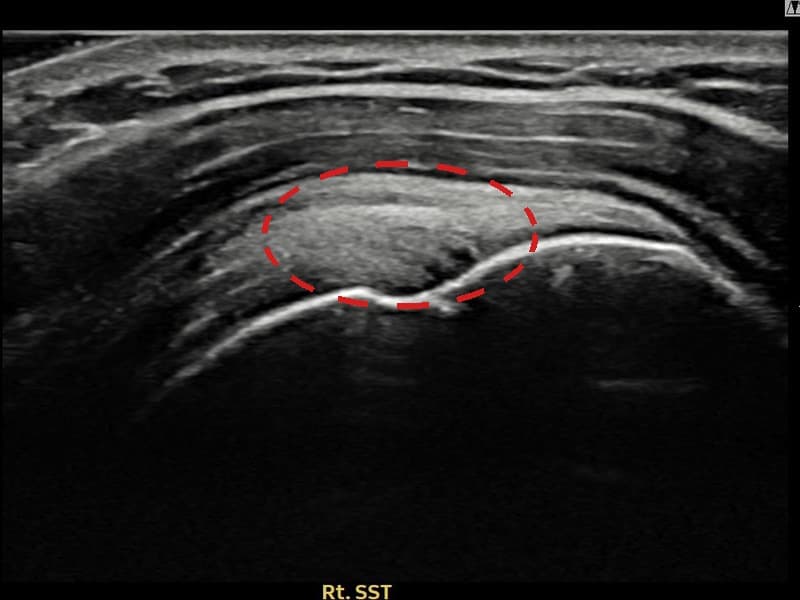

术后

术前超声确认右侧 冈上肌腱 关节面侧部分撕裂,右侧冈上肌腱回声不连续伴肌腱缺损(7mm × 4mm (肌腱厚度约42%缺损))。术后超声显示撕裂部位充满再生组织,肌腱连续性恢复,回声模式正常化。

该患者持续肩痛。详细超声检查确认右侧 冈上肌腱 关节面侧部分撕裂(缺损:7mm × 4mm (肌腱厚度约42%缺损))。在超声引导下实施非手术缩小缝合术。术后佩戴支具约4-6周,随后进行分阶段康复锻炼。随访超声确认肌腱连续性恢复、结构稳定,患者顺利回归日常生活。